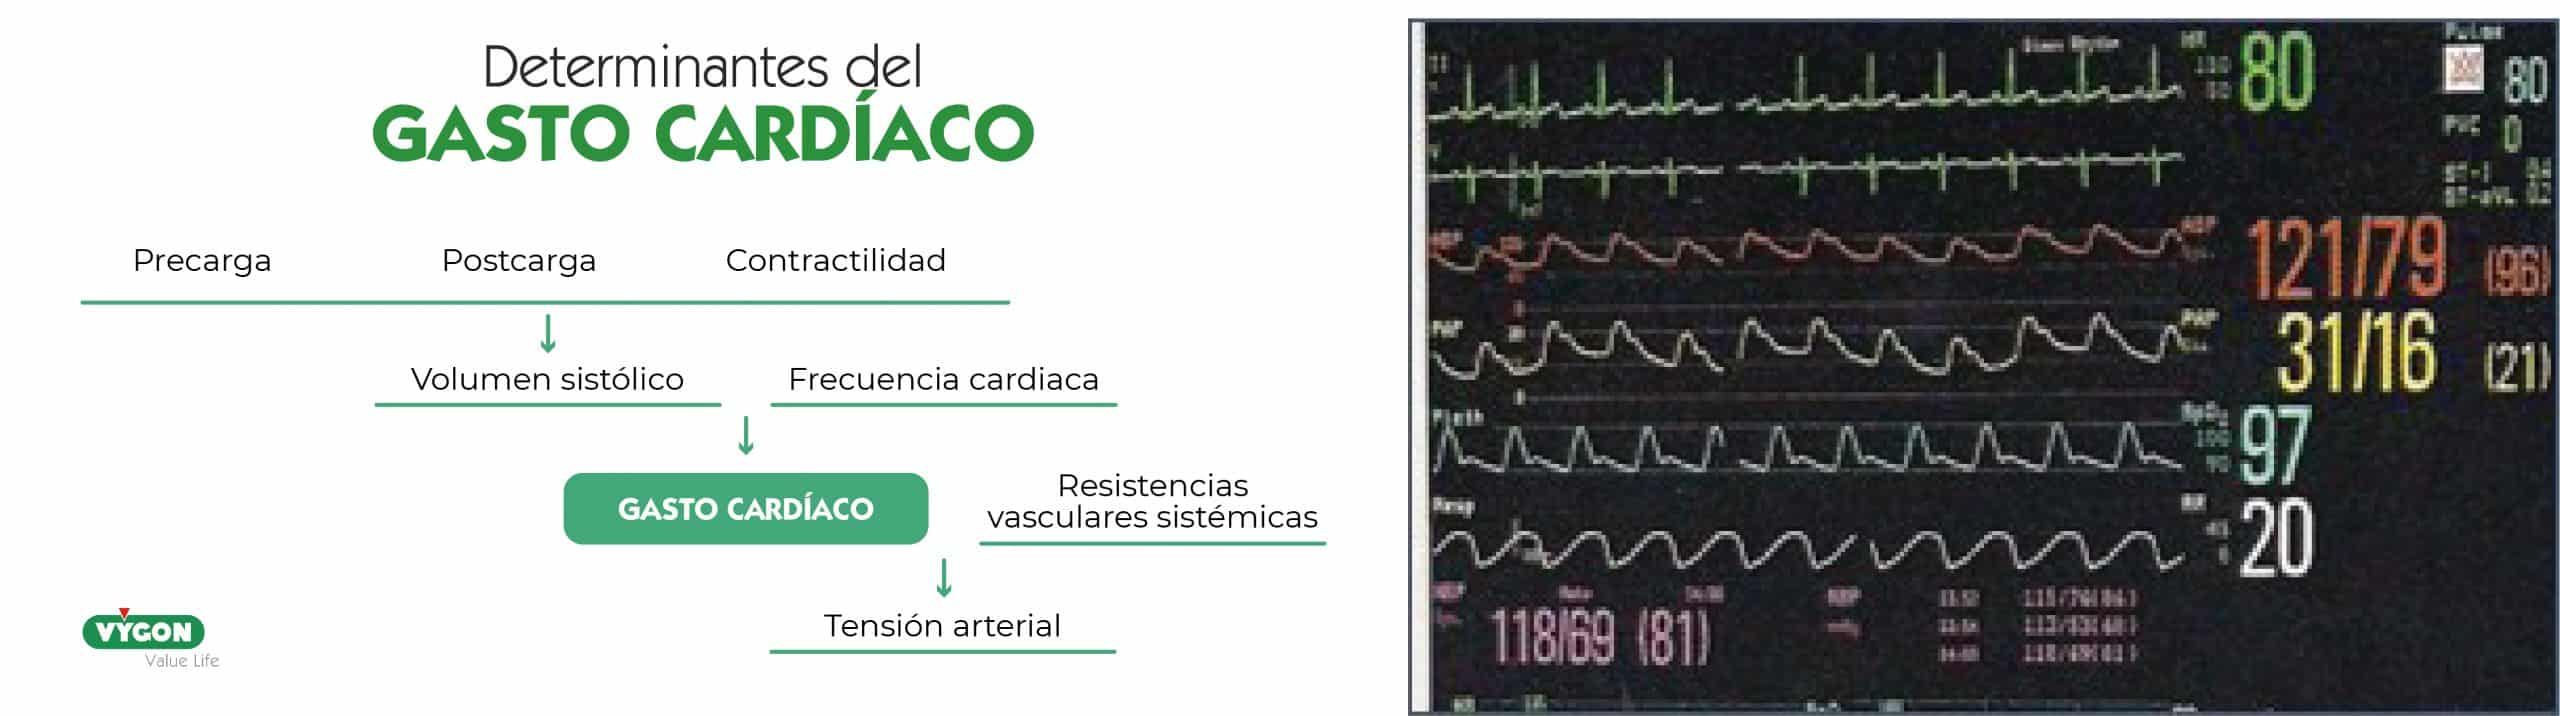

¿Por qué monitorizar?

La monitorización hemodinámica es esencial para realizar un tratamiento apropiado dirigido por objetivos terapéuticos en los pacientes críticos, entre los que se encuentra el postoperatorio de cirugía cardiaca.

La monitorización continua y en tiempo real es imprescindible para la adecuada interpretación y la anticipación en el manejo clínico.

En el postoperatorio de cirugía cardiaca existe gran variabilidad en los datos hemodinámicos, la cual se ve acentuada en niños, sobre todo, en edades precoces como en los neonatos.

El gasto cardíaco tiene que adaptarse a las necesidades de consumo de O2 en cada momento. El paciente crítico tiene unas demandas de O2 anormales debido al proceso de la enfermedad y la fisiopatología de su propia cardiopatía, como sucede en el ventrículo único.

Es fundamental integrar la fisiopatología del paciente con la situación clínica y los objetivos terapéuticos.